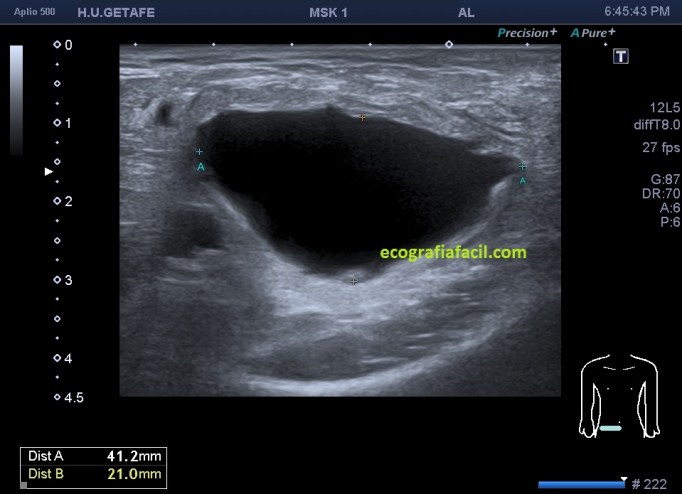

En el caso que te traigo hoy no hizo falta buscar mucho, nada más poner la zona en corte transverso en la región inguinal derecha, cerca de los labios mayores, la paciente tenía una masa blanda, ligeramente dolorosa durante la exploración que había aumentado ligeramente tiempo atrás y que ecográficamente tenía un aspecto anecoico,imagen 1, de paredes finas, más grande en su eje lateral que en el eje antero posterior y que se deformaba con la ligera presión del transductor y que no modificaba su ecoestructura con la maniobra de Valsalva.

En cuanto localicé este hallazgo realicé corte transverso (imagen 2) y longitudinal (imagen 1), con medidas y estudio en modo doppler para ver vascularización (imagen 3, flecha amarilla), seguidamente, era muy importante asegurar algunas referencias locoregionales como los grandes vasos femorales, siempre debemos documentar esta coexistencia y buscar un cuello que puedes observar con las dos flechas rojas de la imagen 1 y que la ecoestructura marca perfectamente al ser anecoica.